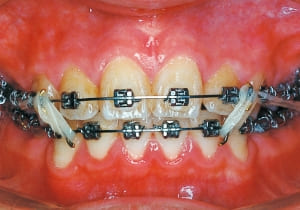

17 At start of full bracket treatment 5-18-’92

18 Treatment progress 4-11-’94

In the maxilla, insufficient space for canine eruption was inevitable, necessitating extraction as part of the treatment plan. The maxillary first premolars on both sides were extracted during routine observation to create space for canine eruption (14). Eventually, the canines erupted and settled into relatively favorable positions (15,19,20). In the mandibular dentition, crowding was also present, leading to extraction of the mandibular first premolars on both sides. Treatment with full bracket was then initiated (17).